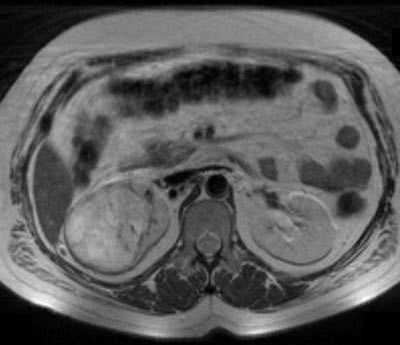

МРТ |

|

МРТ – регионарные лимфоузлы

увеличены до 15-17 мм в диаметре, в желчном пузыре

несколько камней с максимальным размером 6-7 мм